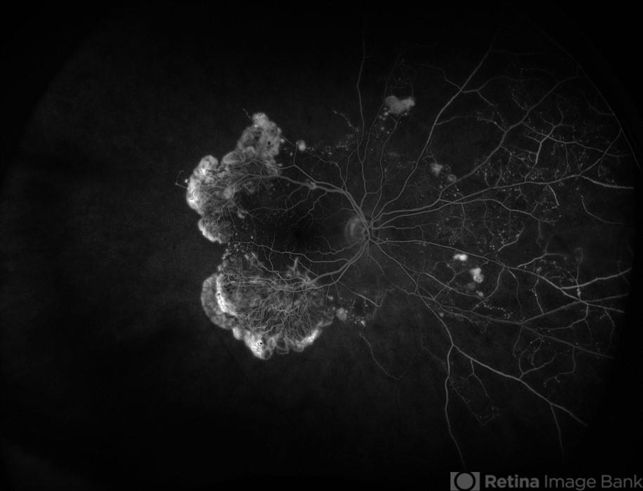

- Diabetic Retinopathy, proliferative diabetic retinopathy (PDR), NVE, neovascularization of the disc (NVD)

- FA of 59 year old female with proliferative diabetic retinopathy.